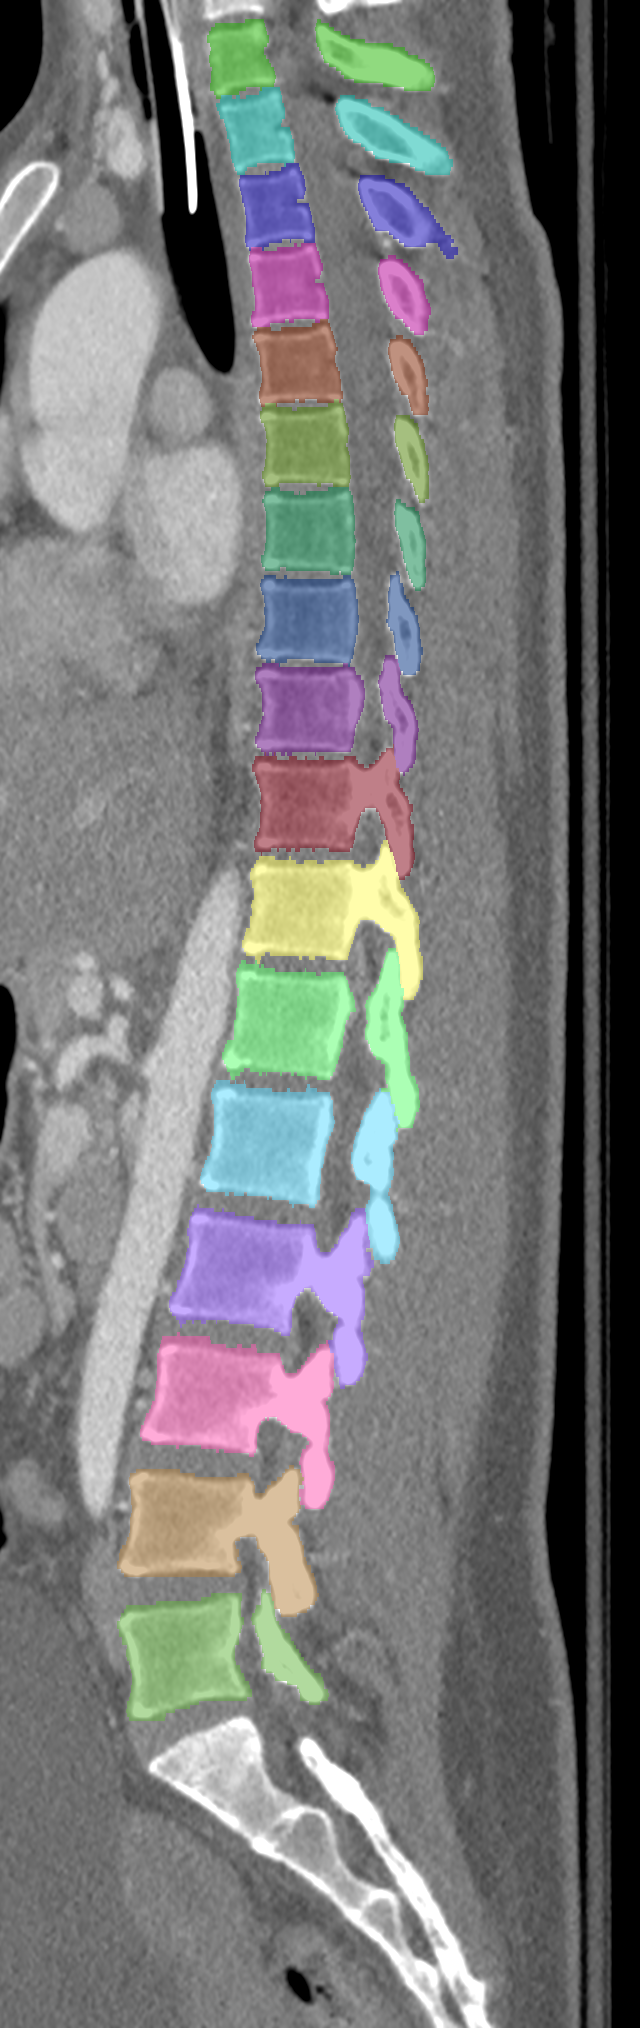

Normalized CT images and reference segmentations of thoracic and lumbar vertebrae from the CSI 2014 workshop

Description

This is the dataset of the vertebra segmentation challenge of the CSI 2014 workshop that was held in conjunction with MICCAI 2014.

- Vertebrae have been anatomically labeled (8 = T1, 9 = T2, ..., 24 = L5)